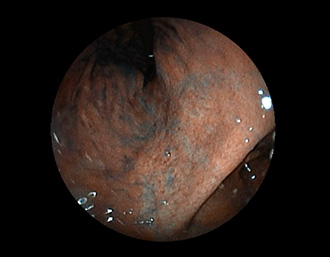

②胃潰瘍(Stage H1)・治療後18日目

胃角部小弯の潰瘍。潰瘍辺縁は平滑で、白苔は部分的に薄い箇所もあり、全周性に再生上皮を認める。